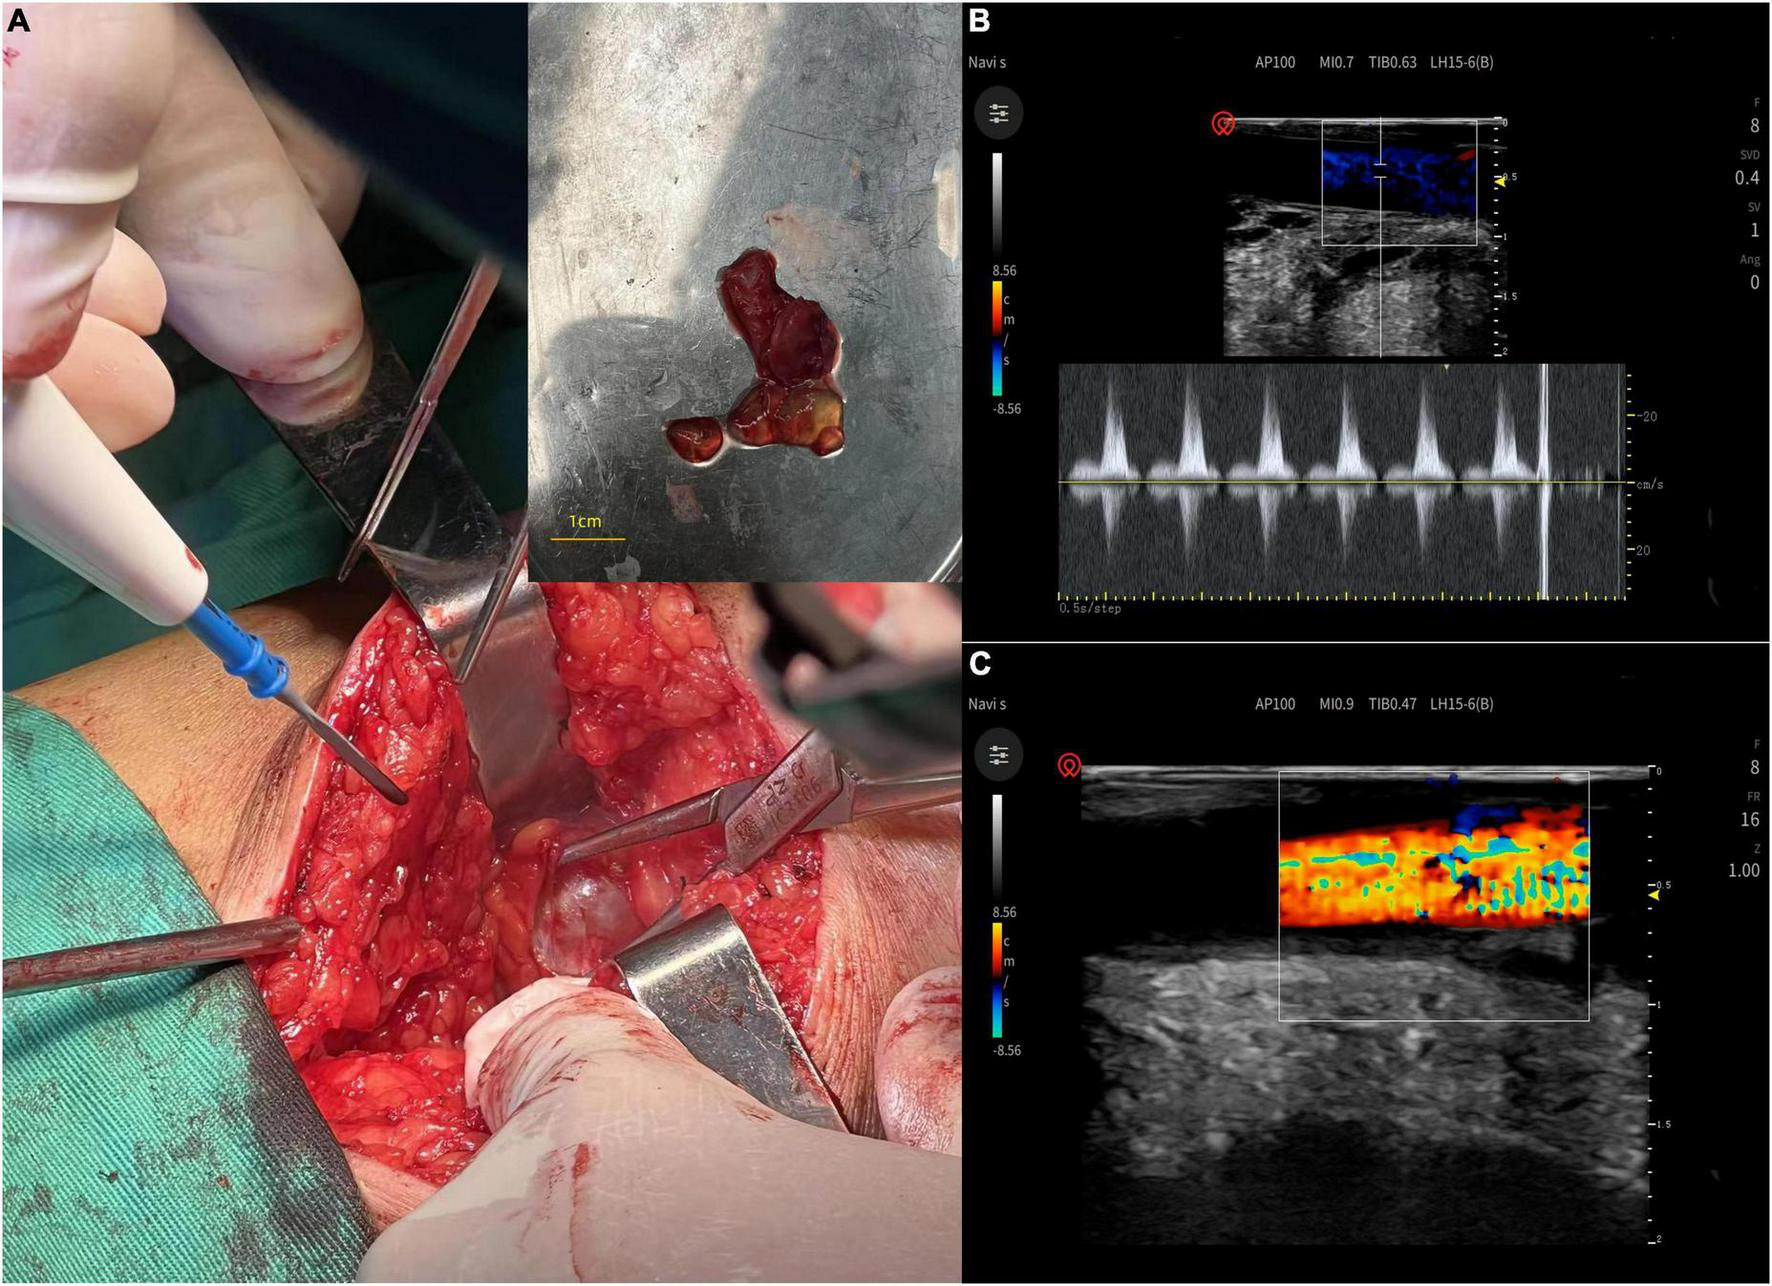

Exploration of the right popliteal artery and cystectomy were performed under epidural anesthesia. The popliteal artery was connected to a tendon sheath cyst on the medial aspect of the long distal head of the biceps femoris tendon with a smooth, tough wall, and jelly-like contents (Figure 3A). After cyst removal, blood flow of popliteal artery and triphasic waves were restored (Figures 3B,C). Postoperative pathology suggests a ganglion cyst (Figure 4).

FIGURE 3

(A) The popliteal artery was connected to a tendon sheath cyst on the medial aspect of the long distal head of the biceps femoris tendon with a smooth, tough wall, and jelly-like contents. (B,C) After cyst removal, blood flow of popliteal artery and triphasic waves were restored.

Here we describe a patient with an IMGC of the biceps femoris muscle compressing the popliteal artery, which could not be diagnosed preoperatively and highlighted the necessity and difficulty of differential diagnosis. Intraoperative exploration and postoperative histopathology are key to the diagnosis of IMGC. In our case, intraoperative ultrasound did not reveal any abnormality in the popliteal artery and there were no clinical symptoms at the 6-month follow-up, and the follow-up ultrasound was normal. In cases where the popliteal artery has been compressed for a short period of time and where there is no thrombosis, intimal thickening, or aneurysm formation, intraoperative ultrasound can be used to determine the flow velocity and flow in the popliteal artery, and if the flow is normal, decompression of the popliteal artery alone can be performed without wall repair or saphenous vein grafting.